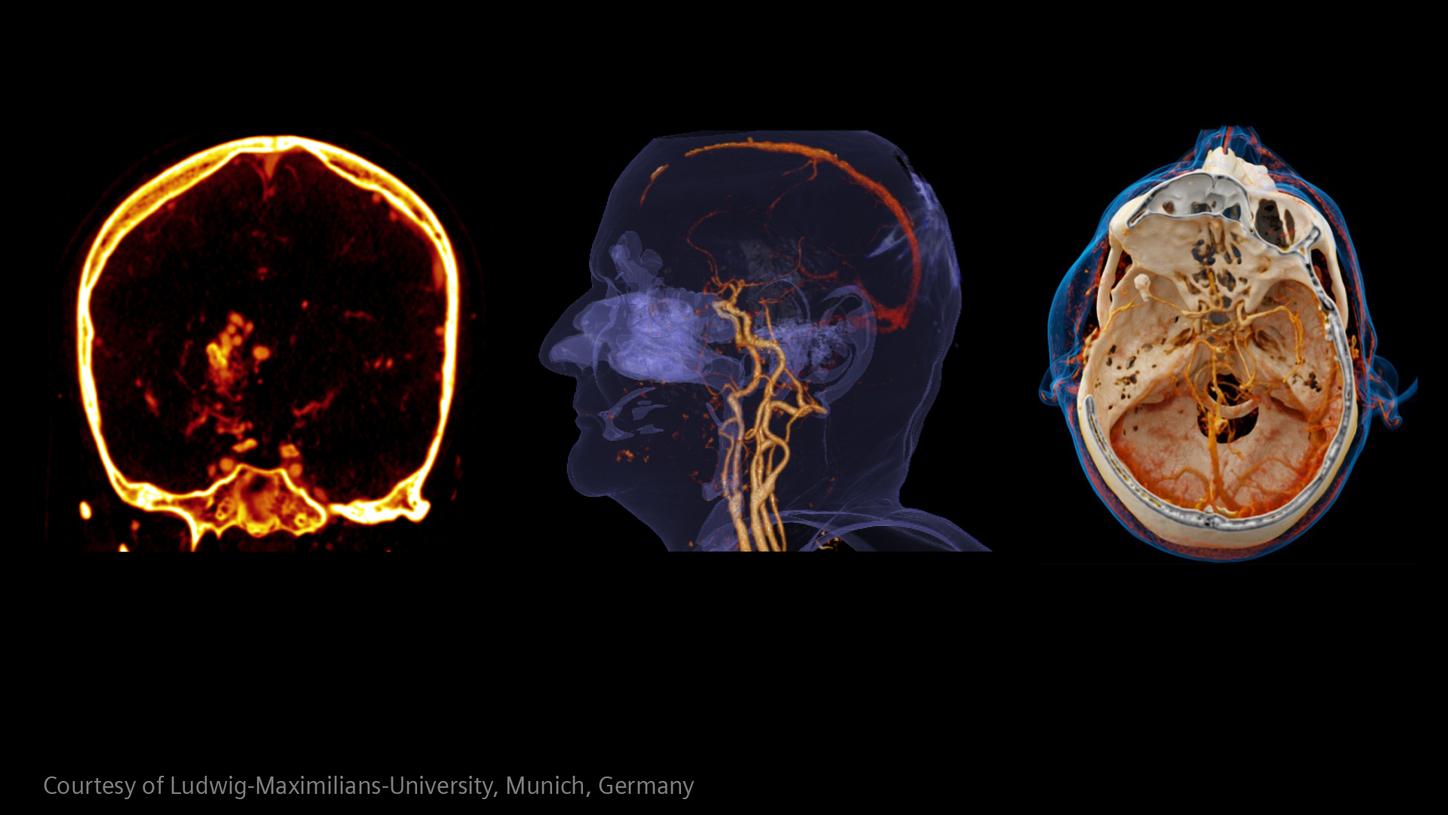

Critical insights in seconds:

How advanced imaging and AI transform stroke workflow

In stroke care, time is brain. Rapid and accurate imaging is crucial to assess the extent of brain injury and guide immediate treatment. Angiography, MRI, CT, ultrasound, and lab diagnostics are essential tools in identifying stroke type, location, and severity. Advances in imaging technology now allow for even faster acquisition, improved resolution, and enhanced visualization of brain tissue and blood vessels. Innovations such as perfusion imaging, real-time vascular mapping, and AI-assisted diagnostics are transforming stroke workflows and enabling precise, timely interventions.